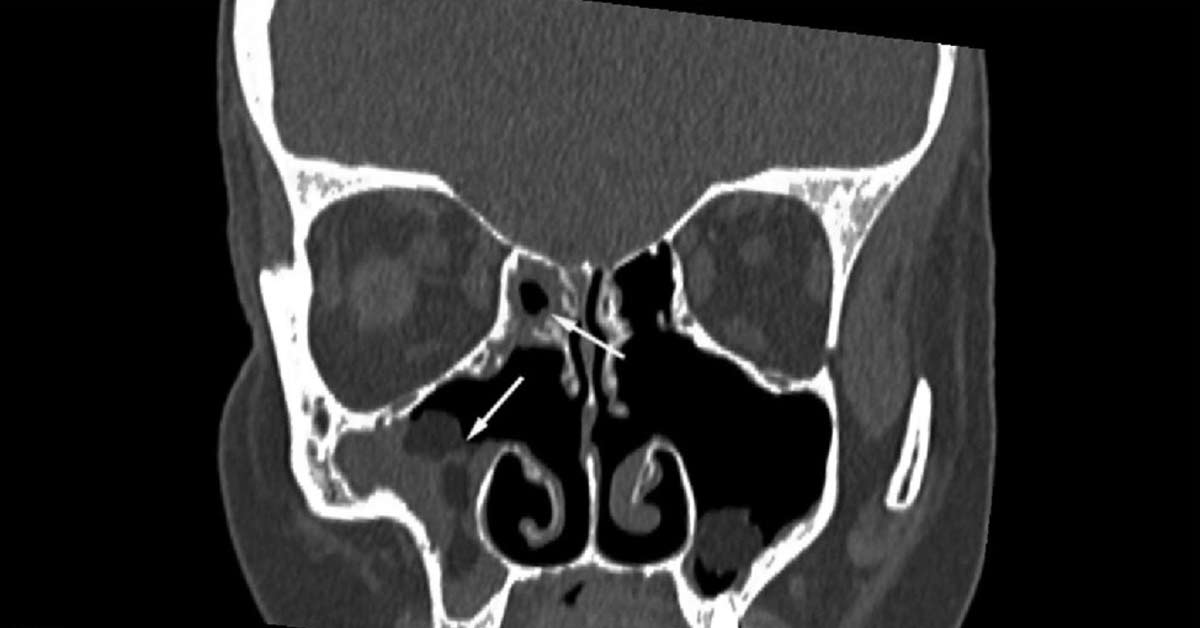

O diagnóstico da sinusite esfenoidal é feito pelo médico com base no seu histórico, exame físico e, frequentemente, em exames de imagem como tomografia computadorizada. É essencial uma avaliação detalhada para diferenciar de outros tipos de sinusite e definir o melhor curso de ação.

A sinusite esfenoidal afeta o seio esfenoidal, localizado no fundo da cavidade nasal, atrás dos olhos. Por isso, a dor pode ser sentida na região da testa, no fundo dos olhos ou na nuca, sendo diferente da dor mais frontal da sinusite maxilar ou etmoidal. O diagnóstico diferencial é chave para o tratamento correto.